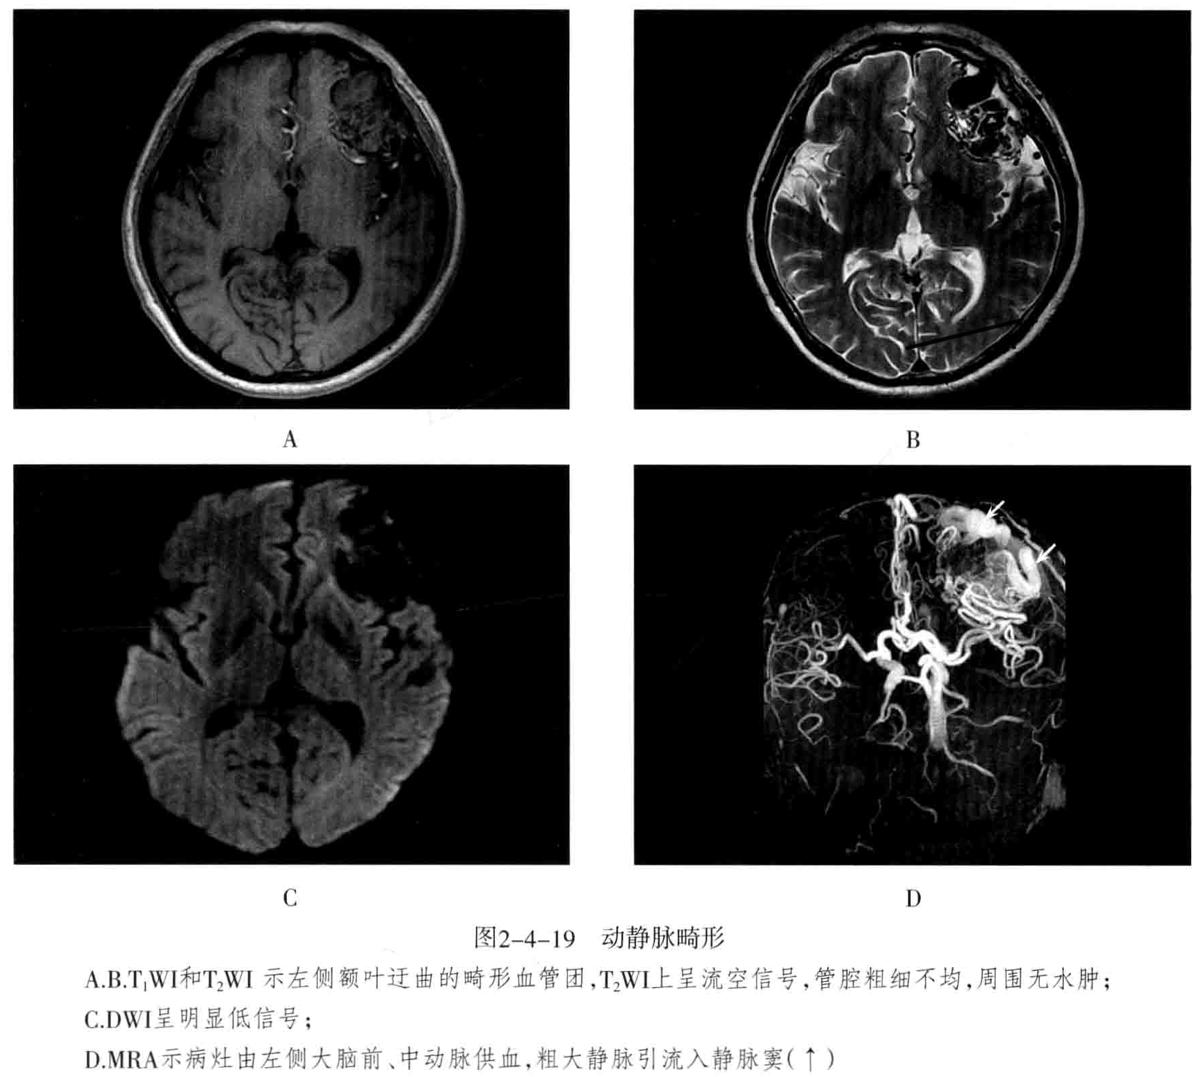

- 海绵状血管瘤 : 病变主要由不规则、大小不等的薄壁海绵状血窦组成,其间有增生的胶质组织,没有正常的神经组织,可反复少量出血,常有不同程度的钙化和含铁血黄素沉着。可发生于脑内(常见于大脑半球各叶)、脑外(常见于颅底)。常无任何症状,或表现为癫痫等。

- CT检查:类圆形高密度或稍高密度病灶,边界清楚,病灶内密度多数不均匀,常伴有明显钙化,呈斑点状或斑块状。病灶周围一般无水肿。增强扫描出现不同程度强化。

- MRI检查:T1WI多呈高信号、稍高信号或混杂信号,T2WI上呈高、低混杂信号,典型者呈“爆米花”状,境界清楚,病灶周围有含铁血黄素沉积,T2WI是表现为低信号环。病灶内及周边无流空血管影。病灶无占位效应,周围脑组织无水肿。大量出血时,表现为病灶短期明显增大,可有占位效应。增强后脑内者病灶可轻度强化,亦可无强化。脑外者多于颅底鞍旁,T1WI低信号,T2WI明显高信号,边界清楚,增强后明显强化且强化均匀。